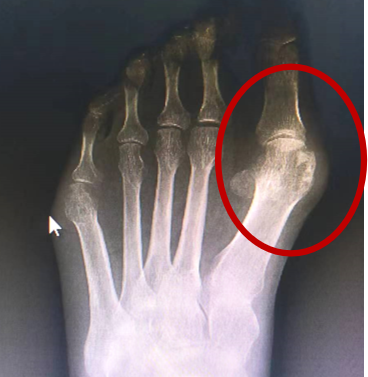

到医院检查后才知道,原来是因为穿高跟鞋太久,大脚趾长期受到挤压而向二脚趾靠拢,导致大脚趾旁多出来了一个“硬骨头”,也就是传说中的“拇趾外翻”。

拇指外翻又称“大脚骨”,外观上是拇趾在第一跖趾关节处向外侧偏斜移位压迫第二脚趾,并且在拇趾内侧出现骨性突起。